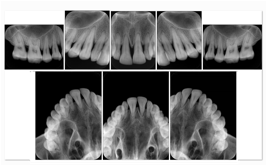

Intra-oral radiography typically involves acquisition of multiple images of various parts of the dentition. Many digital radiographic systems offer customized templates that are used for displaying the images in a study on the screen. These templates may also be referred to as mounts or view sets. The Structured Display Object represents a standard method of encoding and exchanging the layout and intended display of Structured Displays. A structured display object created in this manner could be stored with a study and exchanged with images to allow for complete reproduction of the original exam.

3. A dental provider wishes to capture a series of DICOM IO images for the patient’s dentition. The tooth morphology, teeth are divided into molars, premolars, canines and incisors, and a number of images for each jaw. The anatomic information was captured utilizing the triplet of schema. This standard code sequence is based on ISO 3950-2010, Dentistry - Designation system for teeth and areas of the oral cavity.

Every IO image should have anatomic information either through the primary or modifier sequence.

In most standard cases, images are oriented in structured layouts. These structured displays are useful to be shared between providers for reference purposes.